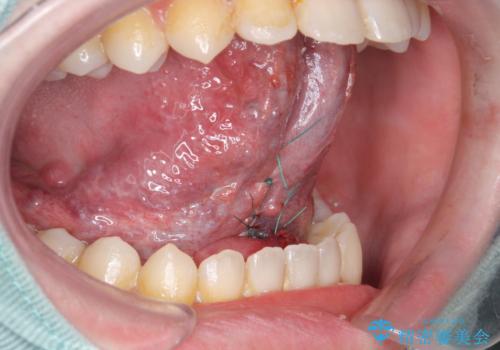

- 滑舌が悪いとの事で来院。

ラ行が言いにくいとの事でしたので舌小帯の形成術を行い、舌の可動域を広げました。

- 舌小帯切除術 3.3万円費用は治療当時の料金となります

舌の動きの範囲が大きくなり、滑舌が良くなりました。

ラ行も言いやすくなったそうです。

舌小帯の形成術は当日に行うことができます。